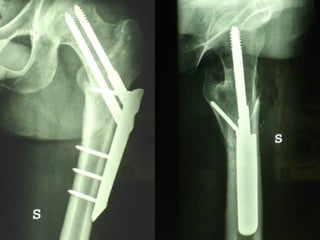

Dal Gennaio 2000 al Dicembre 2005 27 placche LISS di femore

INDICAZIONI COMUNI Fratture sovracondiloidee Fratture intercondiliodee Fratture diafisarie distali PARTICOLARI Fratture con grave osteoporosi Fratture periprotesiche

VANTAGGI CHIRURGIA MININVASIVA Mini Open Inserimento della placca sottocutaneo per scivolamento Viti percutanee Preservazione dei tessuti molli Ridotto danno vascolare Rapida ripresa funzionale

LISS  NCB

NCB